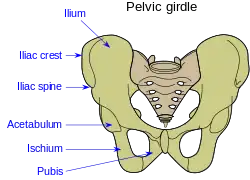

Pubis (bone)

| Pubis (bone) | |

Pelvic girdle | |

Male pelvis with pubis at bottom | |